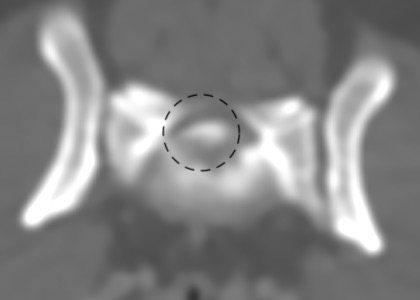

第3-4腰椎間椎間板の脊柱管への突出・石灰化が認められ、右側での脊髄の圧迫所見が認められました。*黒線で囲った部位

責任病変が第5-6腰椎間・第3-4腰椎間の二か所である椎間板ヘルニアと診断しました。